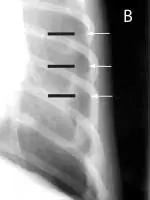

FIGURE 1

Pneumothorax is evident in this thoracic radiograph of a cat (A), as the cardiac silhouette is elevated from the sternum on the lateral projection and the lung lobes are collapsed. Close-up of the lateral view (B) shows air between the sternum and cardiac silhouette. In my experience, the lateral view is more sensitive for detecting pneumothorax because the elevation of the heart from the sternum is easily appreciated. When viewed from dorsoventral (DV) or ventrodorsal (VD) positioning, the lack of blood vessels extending out to the periphery and increased lucency of the lung fields could be overlooked.